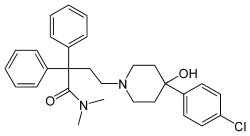

| Opioid peptides | Skeletal molecular images |

|---|---|

| Adrenorphin |  |

| Amidorphin |  |

| Casomorphin | |

| DADLE | |

| DAMGO |  |

| Dermorphin | |

| Endomorphin |  |

| Morphiceptin |  |

| Nociceptin |  |

| Octreotide |  |

| Opiorphin |  |

| TRIMU 5 |  |